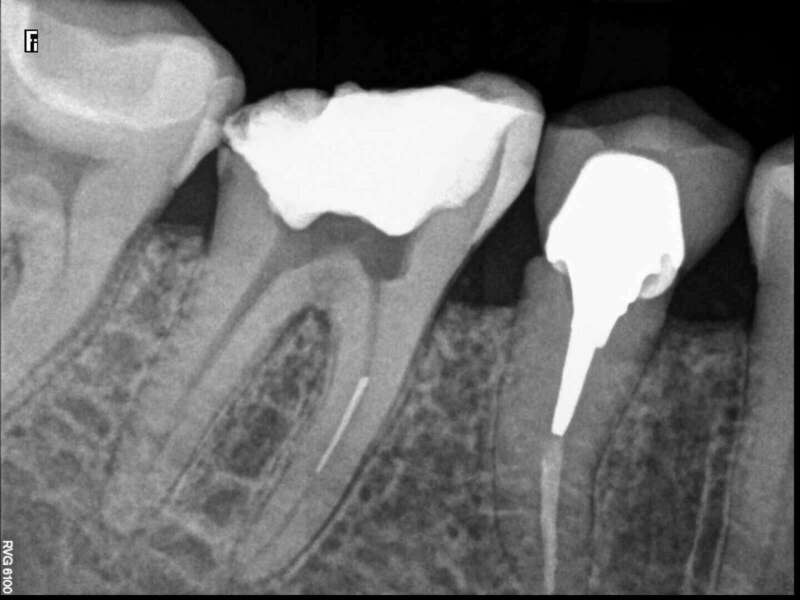

Après